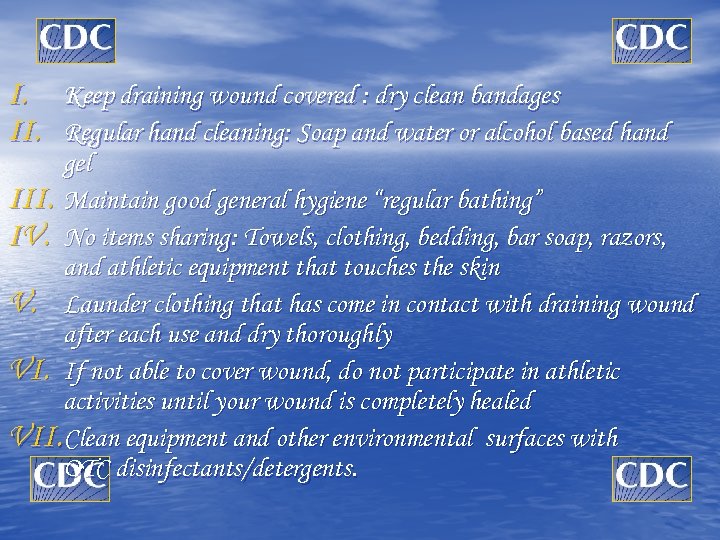

I. Keep draining wound covered : dry clean bandages II. Regular hand cleaning: Soap and water or alcohol based hand gel III. Maintain good general hygiene “regular bathing” IV. No items sharing: Towels, clothing, bedding, bar soap, razors, and athletic equipment that touches the skin V. Launder clothing that has come in contact with draining wound after each use and dry thoroughly VI. If not able to cover wound, do not participate in athletic activities until your wound is completely healed VII. Clean equipment and other environmental surfaces with OTC disinfectants/detergents.

I. Keep draining wound covered : dry clean bandages II. Regular hand cleaning: Soap and water or alcohol based hand gel III. Maintain good general hygiene “regular bathing” IV. No items sharing: Towels, clothing, bedding, bar soap, razors, and athletic equipment that touches the skin V. Launder clothing that has come in contact with draining wound after each use and dry thoroughly VI. If not able to cover wound, do not participate in athletic activities until your wound is completely healed VII. Clean equipment and other environmental surfaces with OTC disinfectants/detergents.